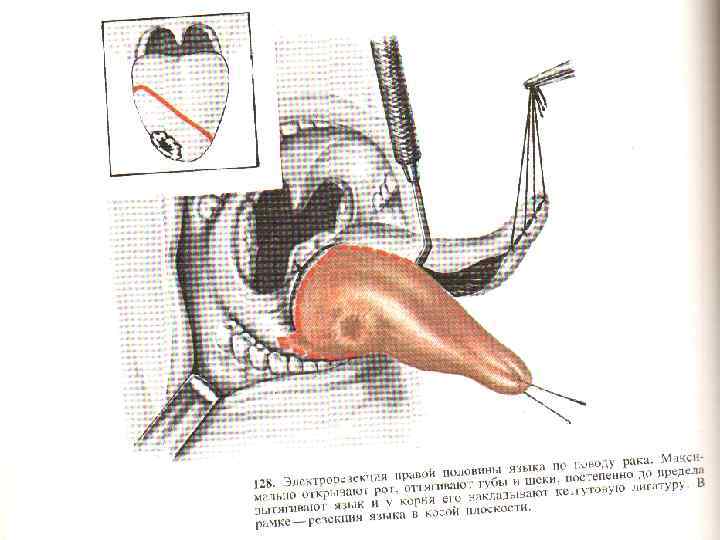

Рак языка 60 -70% - с/3 боковой поверхности и более 20% в корне языка; Плоскоклеточный рак, в корне лимфоэпителиома, аденокарцинома – 1, 5 -3% из малых слюнных желез в языке. Течение рака неблагоприятное, для прогноза имеет значение локализация опухоли. Рак корня языка (III злокачественности плоскоклеточный и лимфоэпителиома) обладает быстрым ростом, дает ранние и частые метастазы в регионарные глубокие шейные лимфоузлы. Рак в среднем и переднем отделах языка (I и II степень) метастазирует в подбородочные, нижнечелюстные и глубокие шейные лимфоузлы

Рак языка 60 -70% - с/3 боковой поверхности и более 20% в корне языка; Плоскоклеточный рак, в корне лимфоэпителиома, аденокарцинома – 1, 5 -3% из малых слюнных желез в языке. Течение рака неблагоприятное, для прогноза имеет значение локализация опухоли. Рак корня языка (III злокачественности плоскоклеточный и лимфоэпителиома) обладает быстрым ростом, дает ранние и частые метастазы в регионарные глубокие шейные лимфоузлы. Рак в среднем и переднем отделах языка (I и II степень) метастазирует в подбородочные, нижнечелюстные и глубокие шейные лимфоузлы

Рак языка (экзофитная форма)

Рак языка (экзофитная форма)